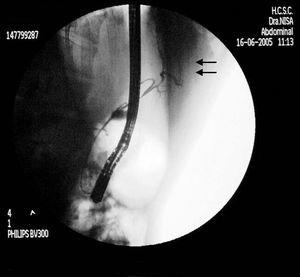

Acude al hospital por patología no relacionada; en la radiografía de tórax presenta patrón intersticio-alveolar compatible con patología crónica pulmonar bilateral. Se realiza tomografía computarizada (TC) torácica que muestra bronquiectasias generalizadas de predominio en pulmón derecho con bronquioloectasias (traqueo-broncomegalia o síndrome de Mounier-Kuhn) y divertículos traqueales. Se observa bilioptisis, confirmada mediante determinación de bilirrubina en esputo (16 mg/dl). En la ecografía abdominal se objetiva aerobilia. En la gammagrafía hepatobiliar se detecta fuga biliar leve a nivel del lóbulo hepático izquierdo, sin actividad en árbol bronquial. Mediante broncoscopio se descubre un bronquio supernumerario en cara interna del bronquio principal derecho, y contenido amarillento de aspecto biliar en bronquio principal izquierdo, que parece proceder del derecho. En TC abdominal aparece un trayecto fistuloso desde el árbol biliar intrahepático izquierdo que sigue por la cisura del ligamento venoso hasta alcanzar la grasa mediastínica, ascendiendo hasta la parte más posterior y medial del bronquio intermediario derecho. La colangiopancreatografía endoscópica retrógrada (fig. 1) muestra un conducto biliar que se dirige desde una rama hepática izquierda, atravesando el diafragma hacia el árbol bronquial izquierdo, con hipoplasia del colédoco. Se implanta una endoprótesis a nivel del colédoco para intentar disminuir el flujo biliar hacia el pulmón.

Figura 1. Colangiopancreatografía retrógrada endoscópica donde se observa el drenaje fistuloso hacia el tórax (flechas).